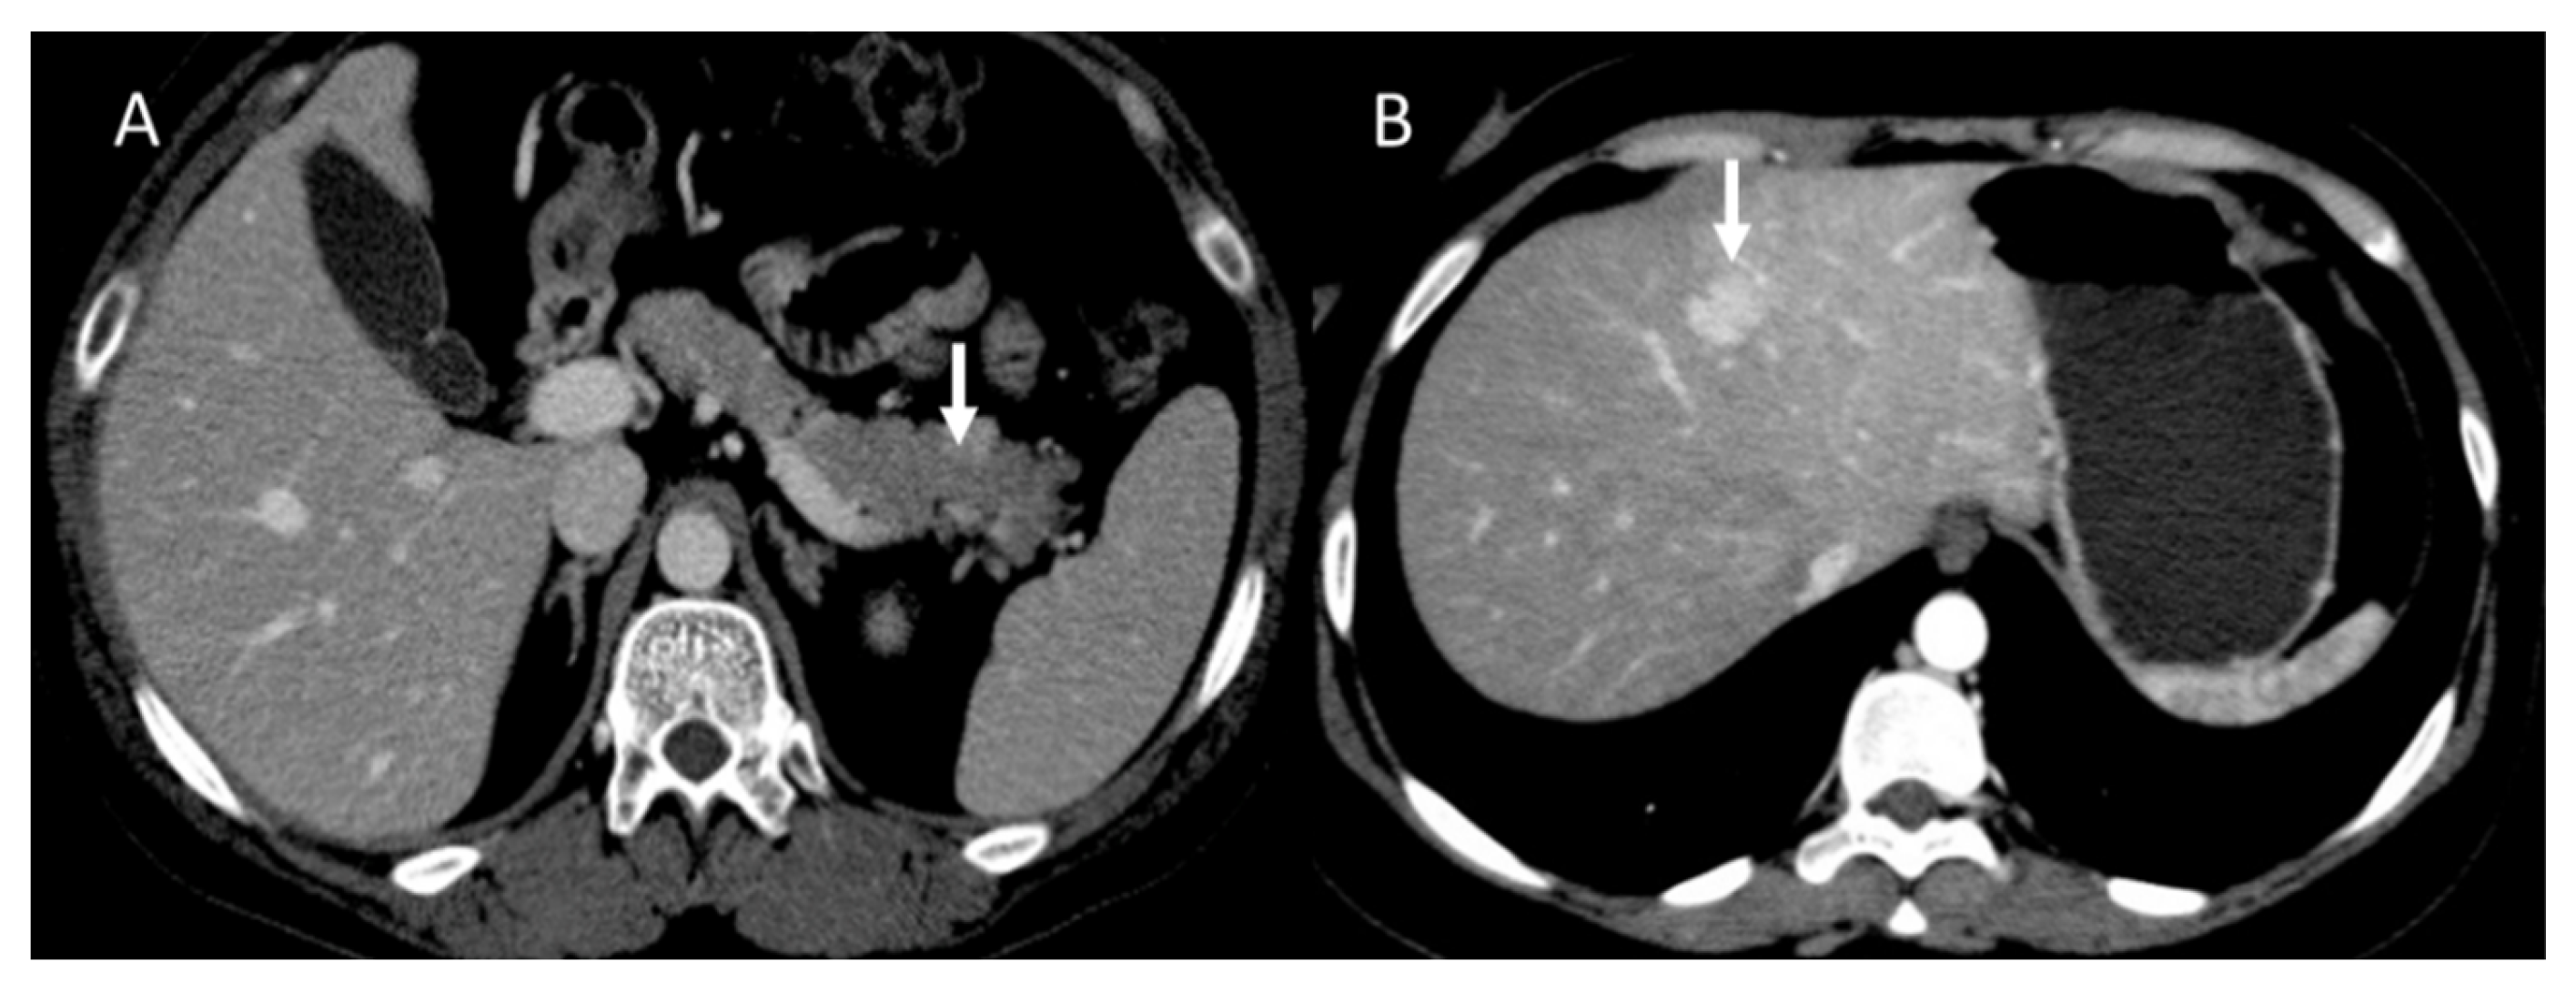

Figure 2.

CT evaluation during portal phase of pancreatic NEN ((A): arrow) with liver metastasis ((B): arrow).